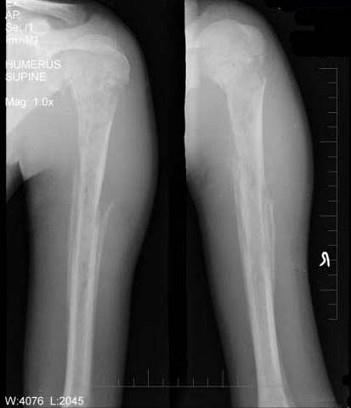

问题 15岁男性患者,畏寒,高热2周入院摄片如图所示,下列诊断正确的是 ( )

选项 A、Ewing肉瘤 B、以上都不是 C、慢性化脓性骨髓炎 D、溶骨性骨肉瘤 E、急性化脓性骨髓炎

答案 E